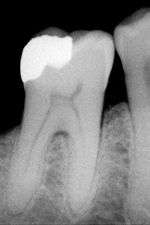

The large amount of mineral in enamel accounts not only for its strength but also for its brittleness.[5] Tooth enamel ranks 5 on Mohs hardness scale and has a Young's modulus of 83 GPa.[3] Dentin, less mineralized and less brittle, 3–4 in hardness, compensates for enamel and is necessary as a support.[6] On radiographs, the differences in the mineralization of different portions of the tooth and surrounding periodontium can be noted; enamel appears lighter than dentin or pulp since it is denser than both and more radiopaque.[7]